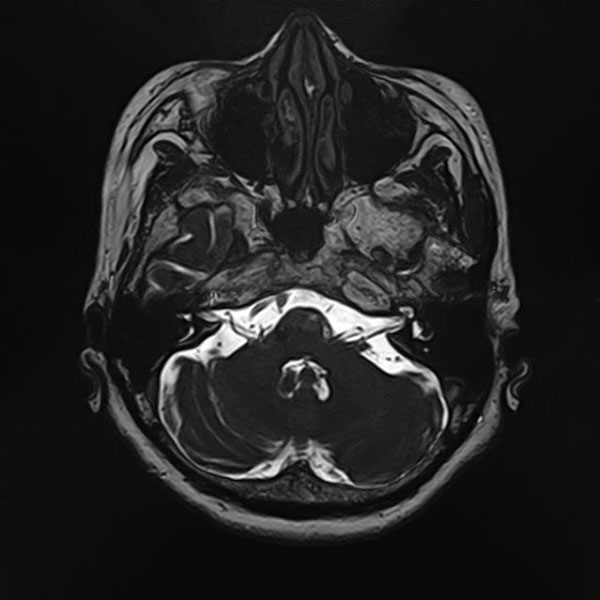

手術前

(MR1)